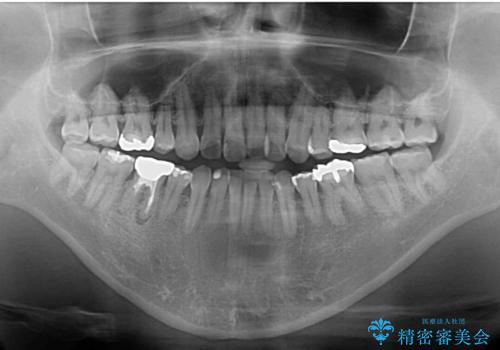

- 抜歯矯正の後戻りを気にして来院された患者様です。

舌の突出癖によるオープンバイトになり、前歯の叢生が後戻りしていました。

舌のトレーニングを行いながら、インビザラインを用いて矯正治療を行うこととしました。

インビザラインの特性を活用して奥歯の咬み合わせを圧下させることで、前歯のオープンバイトを改善さえることができました。